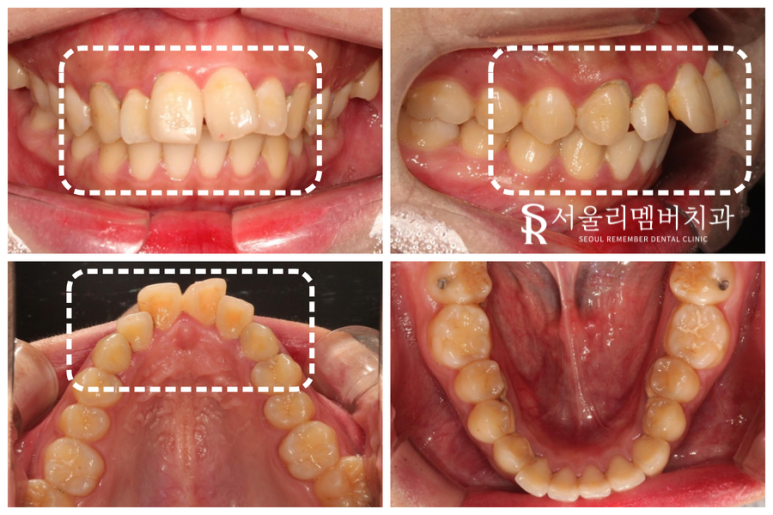

초진 사진을 보면 알 수 있듯이

심한 돌출이 나타난 구내 모습을 확인할 수 있었습니다.

수평피개량이 매우 큰 상태로,

배열 공간이 부족한 것도 확인이 되었는데요.

상악 악궁을 보면 둥글게 자리 잡혀 있어야 되지만

세모꼴로 툭 튀어나와 있는 듯한 모습을 보여주고 있죠.